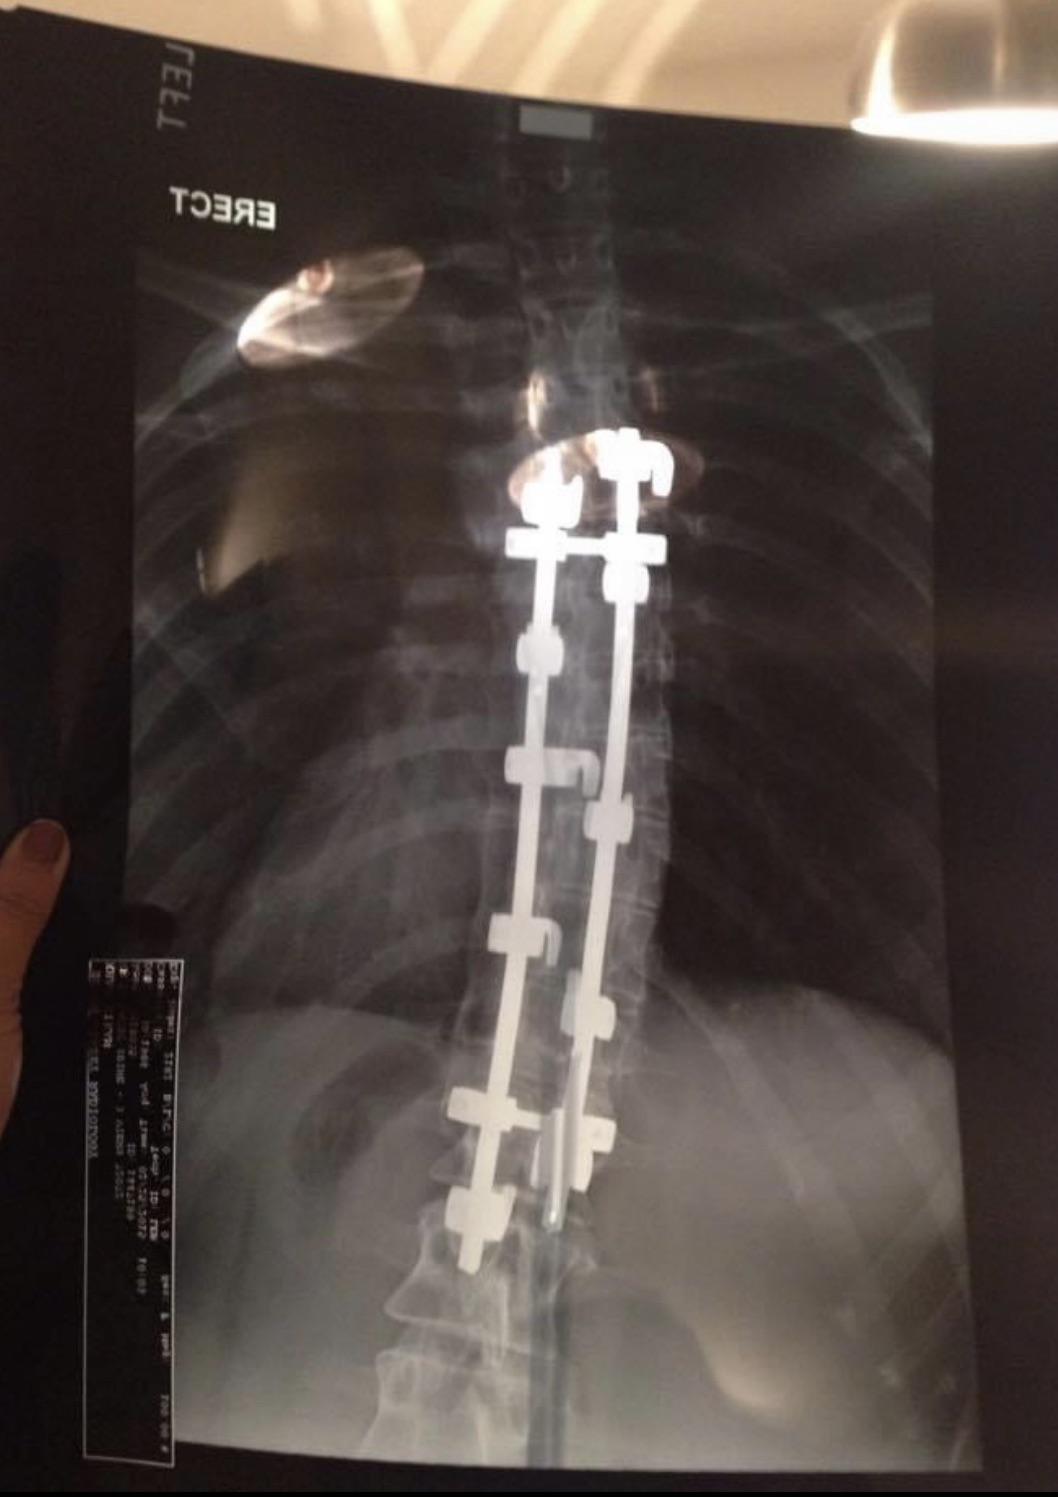

Harrington rod Xray Gabriela L. Flickr

Harrington rod Xray Gabriela L. Flickr Are Harrington Rods Still Used Surgeons trust them due to their. Paul harrington, it was the first device designed to straighten and. Harrington rods implanted are permanent, and if one fails or malfunctions in some way, there is no reversing the procedure. They work well, correcting the curve and enhancing spinal function. The harrington rod for scoliosis is hardware that’s commonly attached to the spine. Are Harrington Rods Still Used.